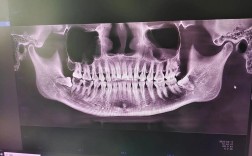

- 精确的术前影像学评估(CBCT)是必须的,确定颏孔和下牙槽神经管的确切位置。

- 术前评估: CBCT确定骨量、神经血管位置、颏孔位置,评估牙龈厚度和生物型。

- CBCT是术前规划不可或缺的工具,用于精确评估骨量和神经位置。